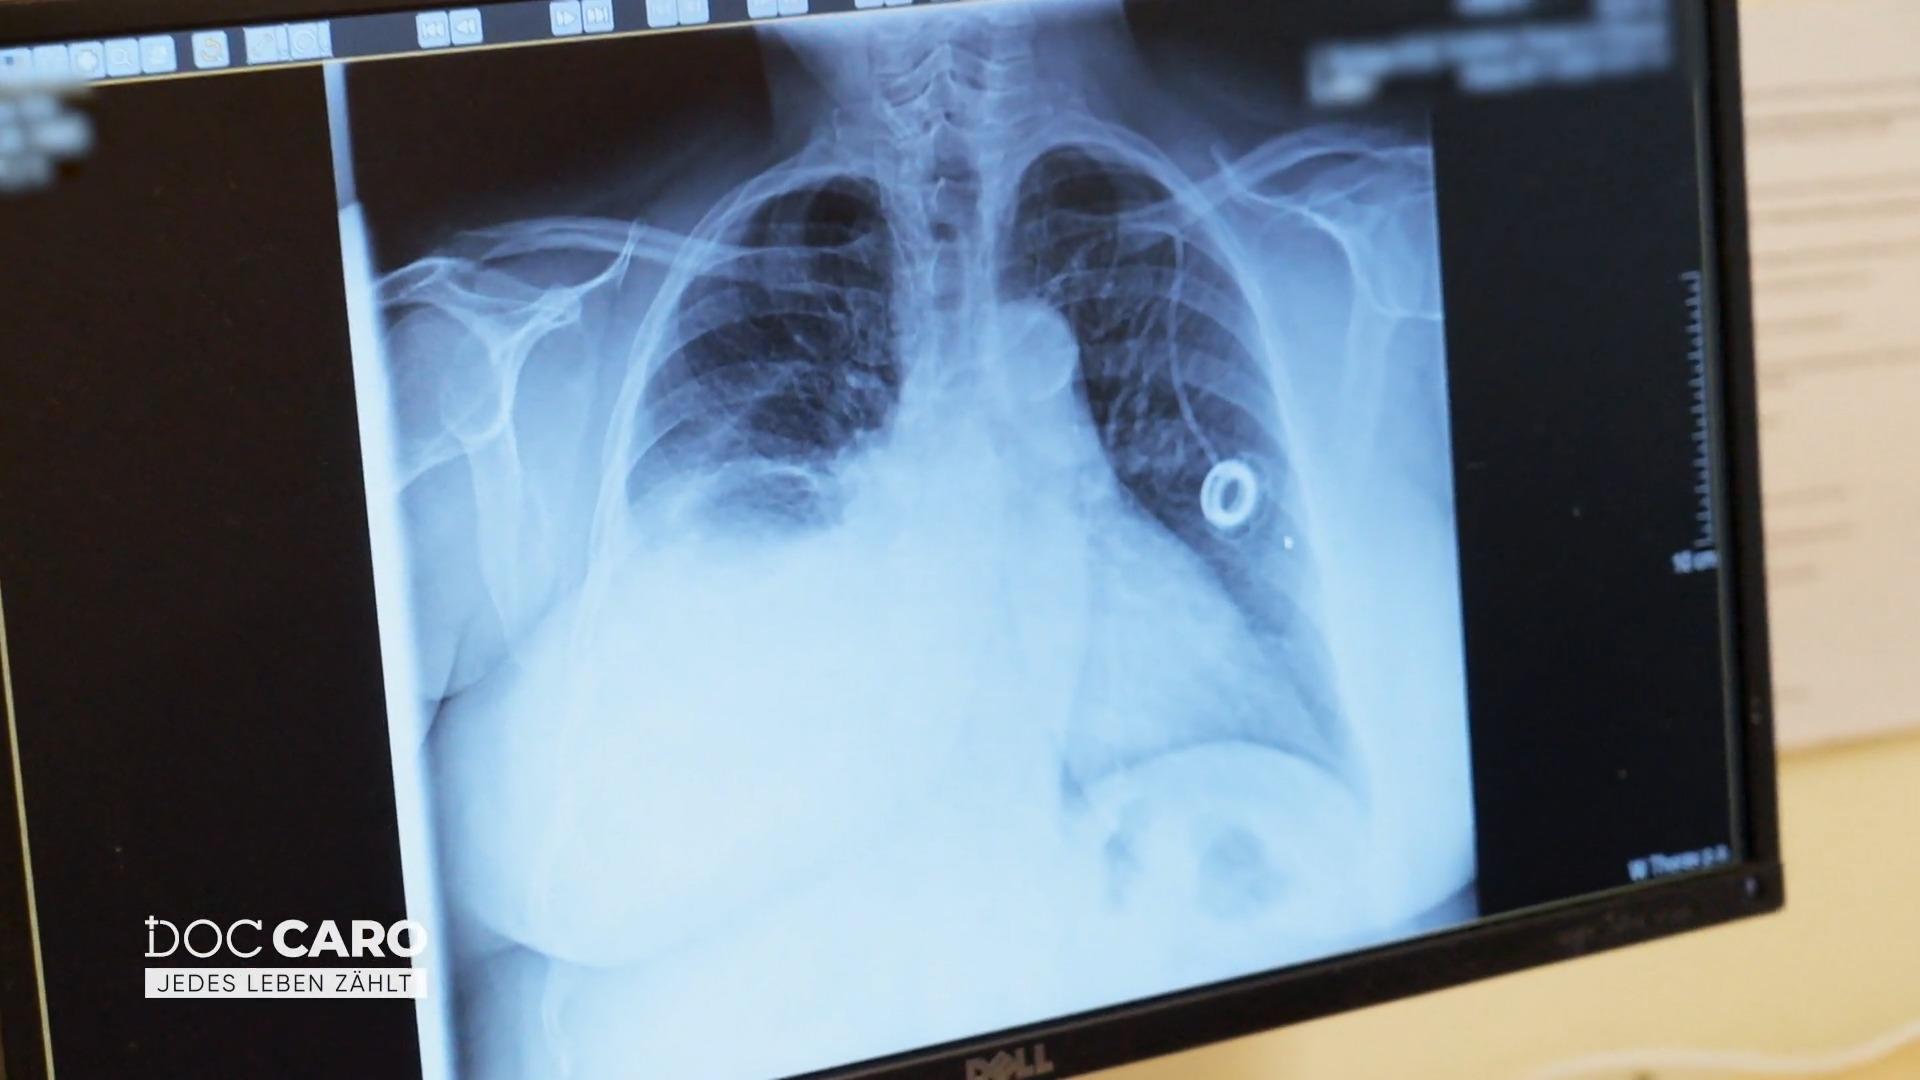

Doc Caro überprüft die Röntgenbilder

"Doc Caro": Seit Wochen leidet eine ältere Frau unter Luftnot. Ihr Hausarzt verweist sie ins Helios St.-Johannes-Klinikum, um ein mögliches Krebsrezidiv abzuklären. Die weitere Diagnostik soll Klarheit bringen.